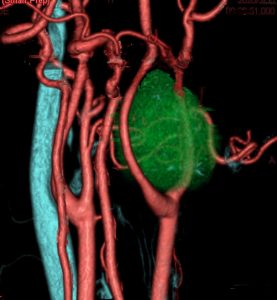

症例:頸静脈孔より下の深頸部のもの:副咽頭間隙腫瘍

左頸静脈孔の下の迷走神経節から発生したものです。ごく軽い飲み込み辛さだけが症状でした。

内頚動脈を強く圧排して,外形動脈からはかなり豊富な血流が流入しています。頭頸部外科で顎骨を割るような手術を計画されていました。

でも,右側の画像で見るような角度から,小さな頸部の皮膚切開だけで,胸鎖乳突筋だけを乳様突起から外して翻展して摘出できました。内部からほじくるように摘出すれば症状悪化はないのですが,周囲軟部組織から切断して剥離しようとすると厳しい嚥下障害と嗄声になります。

手術で全摘出しましたが嚥下障害などはでませんでした。普通のおとなしい神経鞘腫ですから再発はありません。